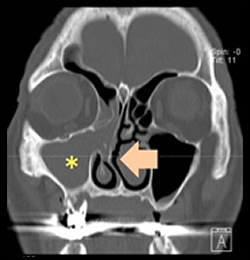

慢性副鼻腔炎(ちくのう症)

ヒトの鼻はいくつもの空洞に分かれており、それらを副鼻腔といいます(図4)。それぞれの副鼻腔は自然口という小さな通路でつながっていますが、この通路が炎症などでふさがると副鼻腔内で炎症を起こし、粘膜が腫れて粘液がたまります。この状態が長引いたものが慢性副鼻腔炎で、膿がたまると蓄膿症という状態になります。たまった粘液がさらに粘膜の炎症を引き起こし、鼻茸(ポリープ)を増生させることがあります(図5)。ポリープによってにおいの分子が嗅神経に届かないと、嗅覚障害をもたらすことがあります。嗅覚が低下すると味も感じにくくなる味覚障害を自覚することもあります。慢性副鼻腔炎を治すことで、嗅覚障害が改善します。

副鼻腔はいくつもの小さい部屋に分かれています。

内視鏡で観察しています。

鼻茸(ポリープ)が確認されています。(黄色*)

体が成長する発育過程において様々な原因で鼻中隔が湾曲して息の通りが悪くなります。外見からはわかりませんが、CTで確認すると(図8)、鼻中隔が大きく曲がっていることが分かります(黄色矢印)。湾曲の程度が軽度の場合には問題ありませんが、重度の場合には片方の鼻閉を常に自覚し、空気の通過障害を起こして粘膜の障害を生じやすくなるといわれています。

鼻腔を閉塞している(∗)

それにより副鼻腔炎も合併している(∗)